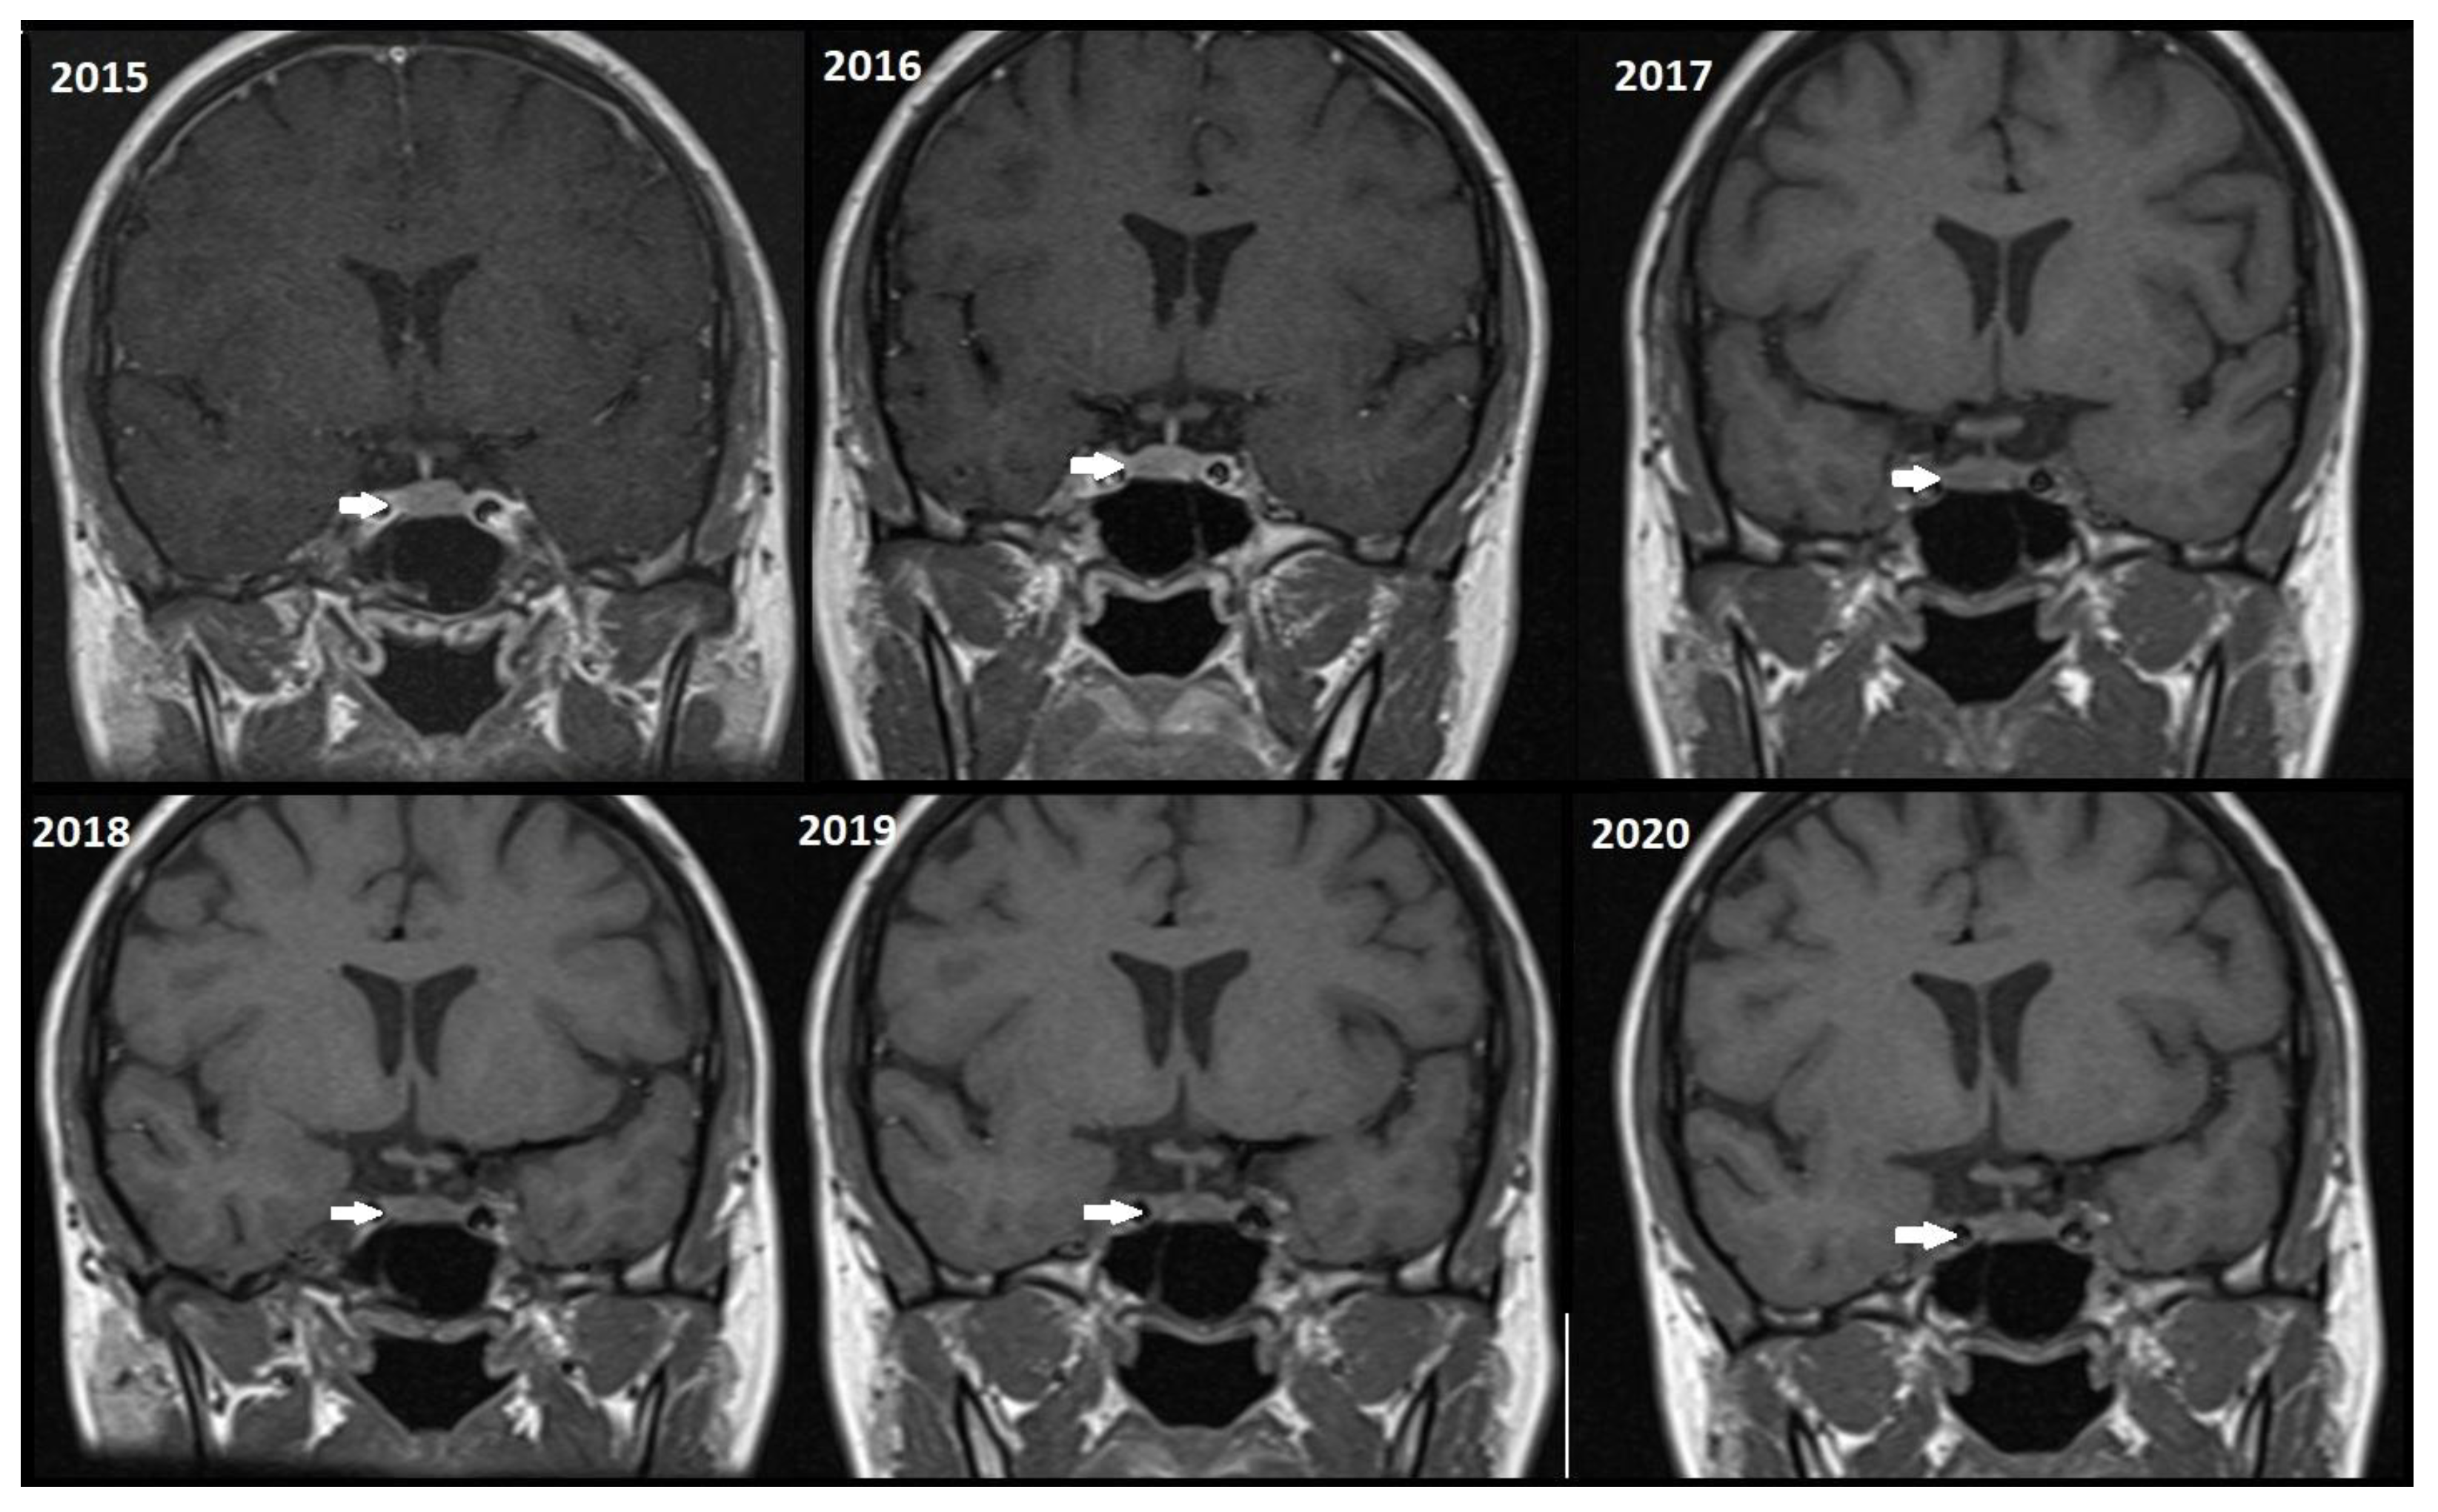

Although, the main cohort contained patients referred between 2020 and 2024, Figure 2, Figure 3 and Figure 4 shows a representative case with historical scans (2015–2020), retrieved from PACS, to demonstrate temporal stability. No evidence of recurrence of tumors in any of the nine who underwent resection of macroadenomas during this period was seen.

Figure 3.

Representative T1W coronal images (2015–2020) of a stable microadenoma (arrows) of a 33 Y/O woman. In the 5 years of follow-up, no size change can be seen.